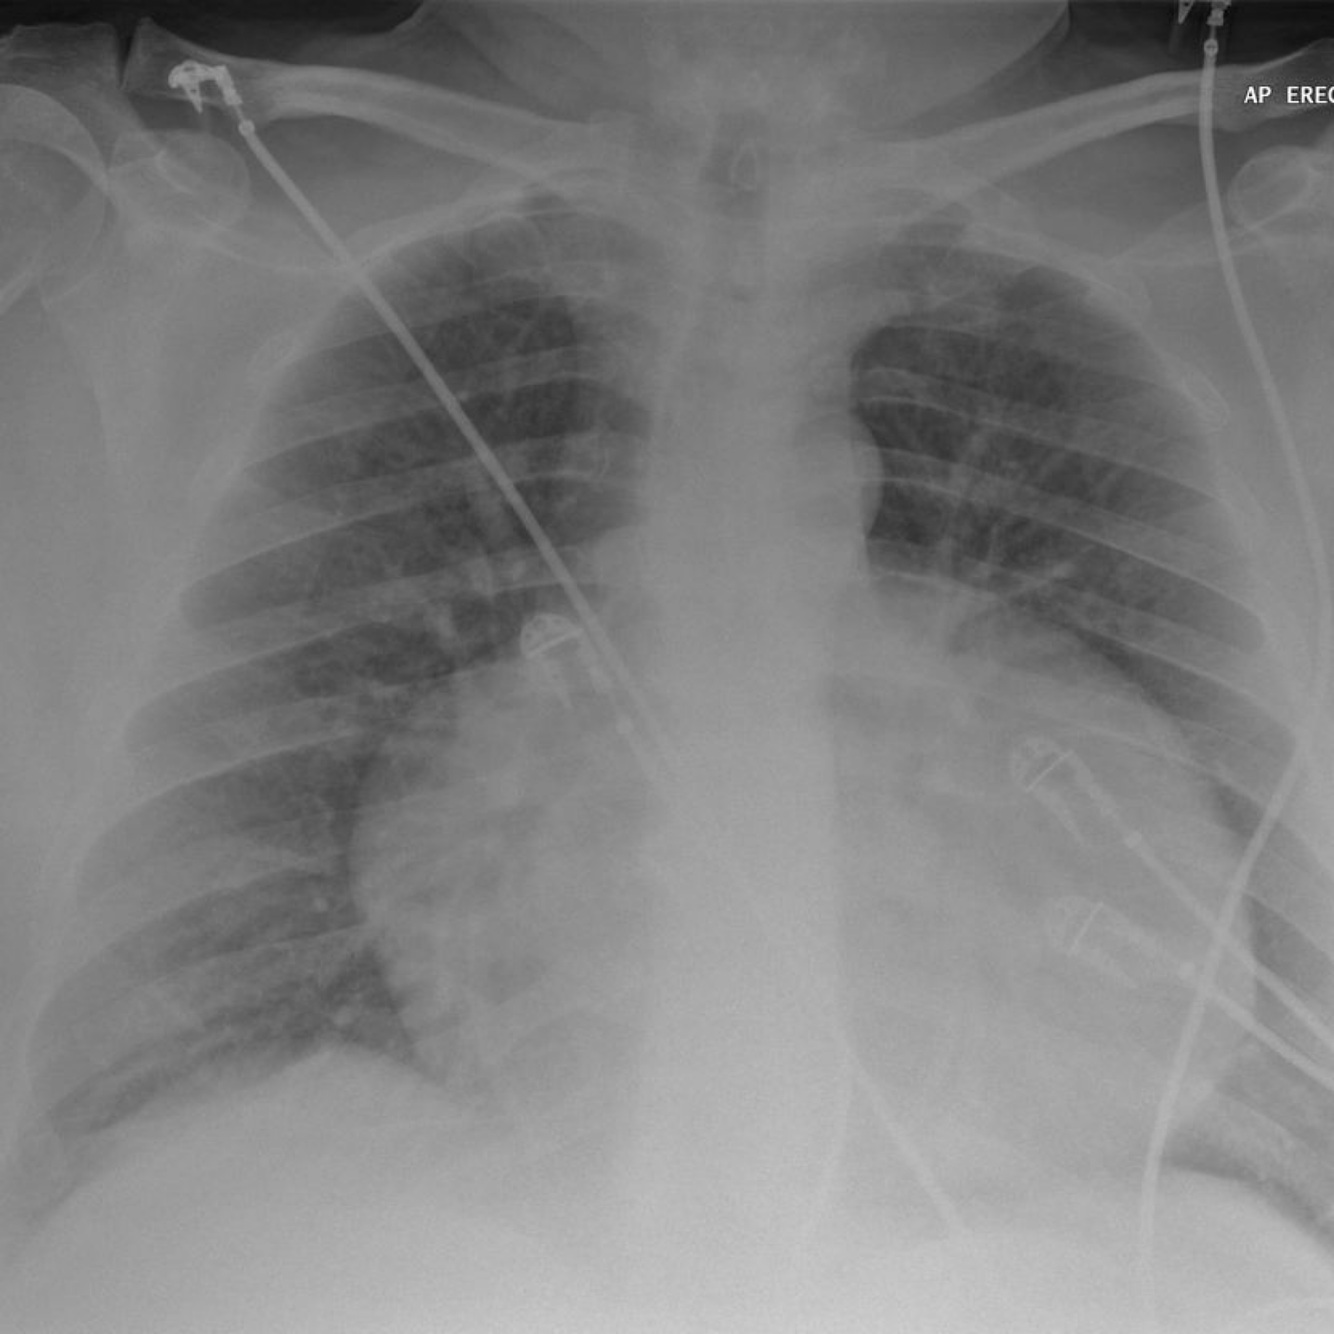

Pulmonary edema